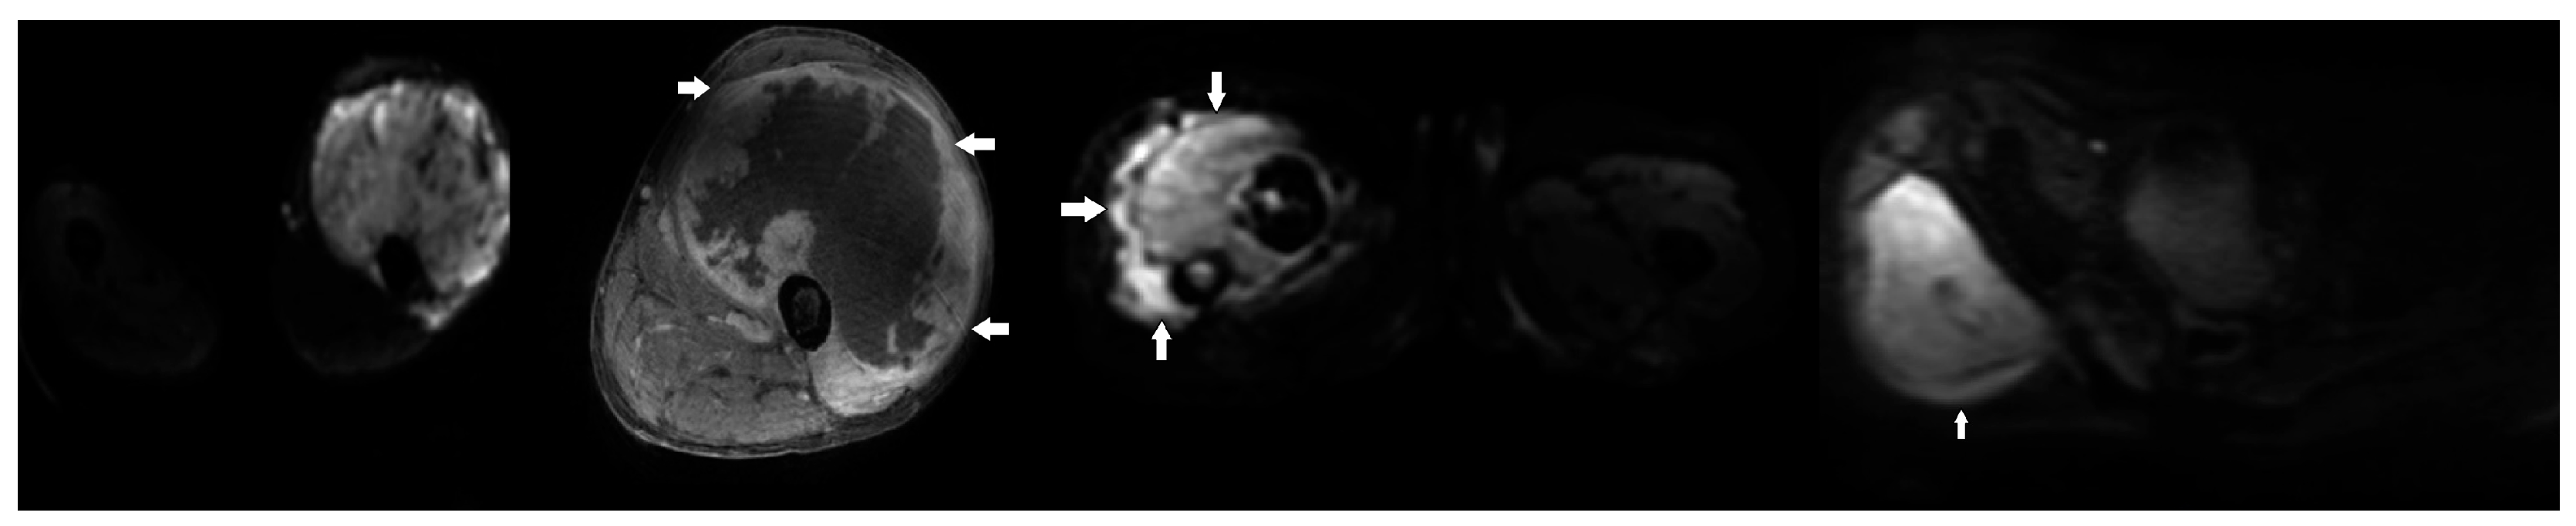

- Hong, J.H.; Jee, W.H.; Jung, C.K.; Jung, J.Y.; Shin, S.H.; Chung, Y.G. Soft tissue sarcoma: Adding diffusion-weighted imaging improves MR imaging evaluation of tumor margin infiltration. Eur. Radiol. 2019, 29, 2589–2597. [Google Scholar] [CrossRef] [PubMed]